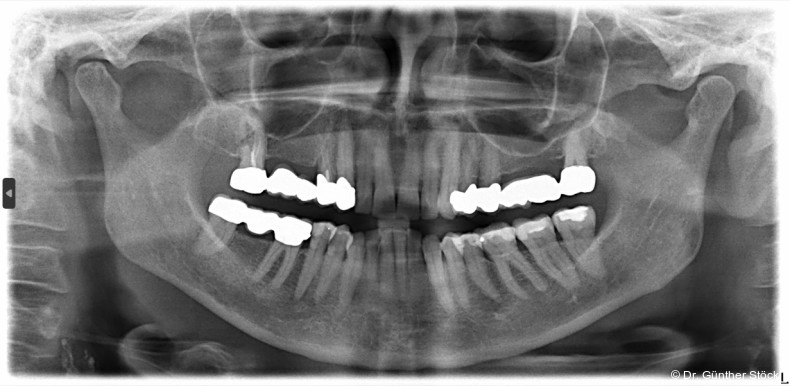

Mikroleakages, die aus einem unzureichenden Verschluss resultieren, stellen eine der ­Haupt­ursachen für endodontische Misserfolge dar. Eine zentrale Komponente zur Erreichung eines dichten Verschlusses ist der Wurzelkanalsealer. Der Autor nimmt uns mit auf eine Zeitreise dieses ­Materials – in Teil 1 vom Start mit MTAs bis hin zu modernen Biokeramiken und ihren ­grund­sätzlichen Eigenschaften.

Die Funktion des Wurzelkanalsealers besteht darin, die Hohlräume zwischen dem Kernfüllmaterial und den Dentinwänden zu füllen und eine dichte Verbindung herzustellen.14 Insbesondere die Penetration des Sealers in die Dentin­tubuli und anatomische Komplexitäten des Kanalsystems ist für eine suffiziente Versiegelung von entscheidender Bedeutung. Zu den Anforderungen zählen eine exzellente Versiegelungsfähigkeit, dimensionale Stabilität, Biokompatibilität, Unlöslichkeit gegenüber Gewebsflüssigkeiten, eine gute Adhäsion an den Kanalwänden sowie eine adäquate Verarbeitungszeit und einfache Handhabung.9, 10

Die Limitierungen von MTAs motivierten die Weiterentwicklung von Materialien, die auf dem Kalziumsilikat-Prinzip basieren, aber verbesserte Eigenschaften aufweisen.17 Die ersten speziell als Wurzelkanalsealer konzipierten Kalzium­­silikat-­zemente wurden im Jahr 2007 vorgestellt. Diese Materialien, zusammenfassend als Biokeramiken bezeichnet, werden nach ihrer Interaktion mit dem Gewebe als bioinert, biokompatibel oder bioaktiv klassifiziert.9 Moderne biokeramische Formulierungen basieren auf Kalziumsilikaten, Kalziumphosphat und Kalziumhydroxid, wobei als Röntgenkontrastmittel häufig Zirkoniumoxid anstelle von Bismutoxid verwendet wird, um Verfärbungen zu vermeiden. Ihr wesent­licher Vorteil ist die Bioaktivität: Bei Kontakt mit Gewebs­flüssig­keiten initiieren sie die Bildung von Hydroxylapatit, was zu einer chemischen Anbindung an die Dentinstruktur führt.17 Zudem schaffen sie durch die Freisetzung von Kalziumionen und Hydroxidionen ein hochalkalisches Milieu, das den periapikalen Heilungsprozess begünstigt.9 Diese Weiterentwicklungen führten zur Verfügbarkeit verschiedener Konsistenzen, darunter fließfähige Sealer und formbare Putty-Materialien für spezielle Repa­ratur­indika­tionen. Insbesondere die hydrau­lischen Kalziumsilikat-Sealer haben zudem vereinfachte Obturationstechniken, z. B. die Single-Cone-Methode, wieder in den Fokus der klinischen Anwendung gerückt.10

Die fundamentalen Eigenschaften biokeramischer Materialien sind in ihrer chemischen Zusammensetzung und der ­daraus resultierenden Abbindereaktion verankert. Moderne Formulierungen basieren vorwiegend auf Kalziumsilikaten wie Trikalzium- und Dikalziumsilikat, häufig ergänzt durch Kalzium­alu­mi­nat, Kalziumoxid und Kalziumphosphat.1, 17 Eine wesentliche Weiterentwicklung gegenüber dem ursprüng­lichen MTA ist der Ersatz von Bismutoxid als Röntgen­kontrast­mittel durch Zirkoniumoxid oder Tantaloxid, wodurch das ­Risiko von Zahnverfärbungen, eine signifikante Einschränkung früherer Kalziumsilikatzemente, minimiert wird.17 Als hydrau­lische Kalziumsilikatzemente (HCSCs) benötigen diese Mate­rialien für ihre Aushärtung die Anwesenheit von Feuchtigkeit, was im endodontischen Milieu von erheb­lichem Vorteil ist.12 Bei Kontakt mit Gewebsflüssigkeiten oder der im Dentin vorhandenen Feuchtigkeit wird eine Hydrata­tions­reak­tion initiiert. Dieser Prozess führt zur Bildung eines Kalzium­silikat­hydrat-­Gels sowie zur Freisetzung von Kalzium­ionen (Ca2+) und Hydroxid­ionen (OH−), was zur Entstehung von Kalzium­hydroxid als Nebenprodukt führt. Dieser zen­trale Mechanismus bildet die Grundlage für nahezu alle weiteren physikalischen und biologischen Eigenschaften des Materials.9, 17 Die physikalisch-chemischen Eigen­schaften sind für die klinische Handhabung und die Langzeitstabilität der endodontischen Versorgung von entscheidender Bedeutung.